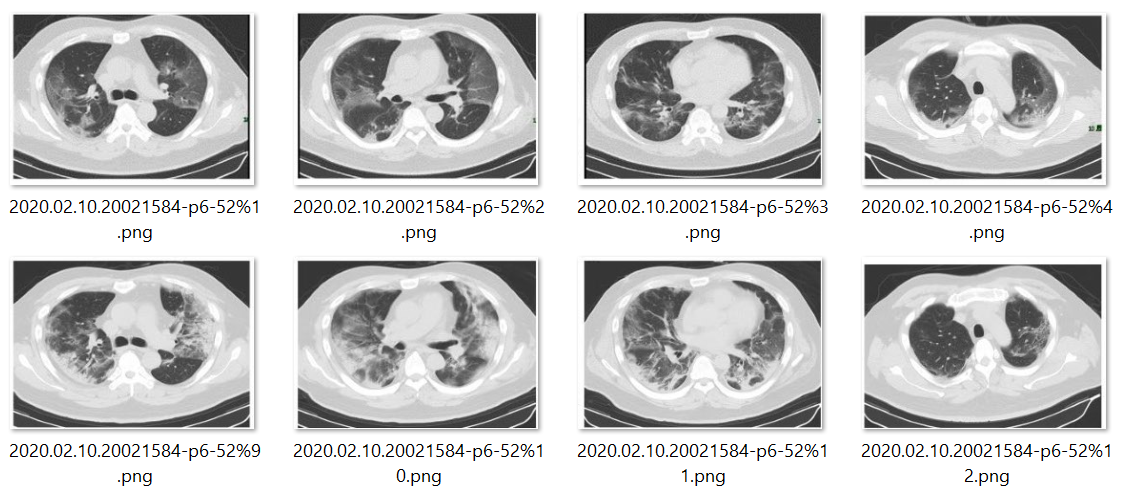

- CT图片

在我们的代码库中包含了一个数据集,在该集合中标有COVID-19阳性特征的CT图像共有349例(Case),而标有COVID-19阴性特征的CT图像共有397例(Case)。这些数量超过了作者在公开报告中所列出的数据统计结果(Reference),推测可能后续又增加了部分样本。然而这些数据量仍然显得较为有限(Implication),基于如此少量的数据进行模型训练难以达到预期的效果(Expectation)。因此建议首先利用外部公开数据对模型进行预训练(Pre-training),随后再通过迁移学习的方法来提升对COVID-19识别任务的能力(Task))。

图4.图片一瞥